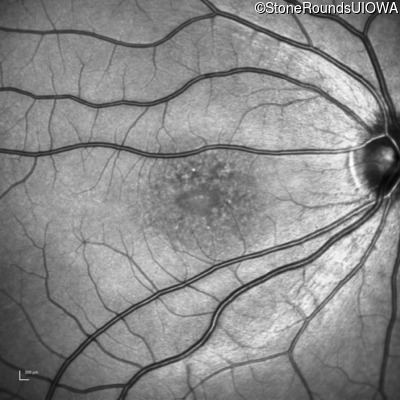

Infrared Fundus Photograph - Right - 20/32

Exemplar